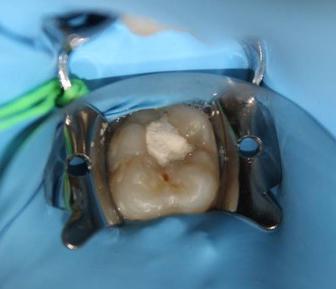

8.Biodentine®AnalternativeinVitalPulpTherapyinYoungPermanentTeeth.ClinicalCase,40monthFollow-Up. (Pgs.88-96)

Biodentine®UnaalternativaenlaTerapiaPulparVitalenDientesPermanentesJóvenes.CasoClínico.Seguimientode40Meses.

LuisDavidRamosFlores,DDS,